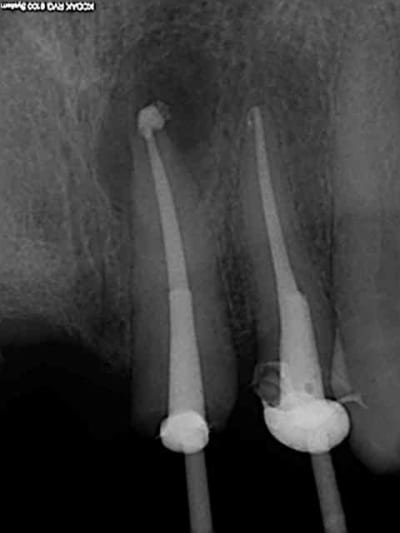

Bridge descellé, re-scellé plusieurs fois par plusieurs dentistes différents. la charte de bonne pratique est respectée (vu qu'on ne fait pas de prothèse) on re-scelle sur de la merde.

Bonjour l'odeur dans les canaux, Il fallait bien qu'il y en ai un qui y mette un terme.

Bien sur l'essentiel porte sur la ventilation des honoraires du bridge à refaire.

Je ne fais jamais de cathétérisme manuel, ca évite de casser des limes 15 de merde dans les canaux. d'ailleurs je ne sais pas ou elle est passée celle là, quelque part dans l'aspi je suppose.))))))

Reprise au R25 puis R40.

Charte de bonne pratique de merde, qui intéresse tout sauf la pratique. Ca m'énerve.

@Chicot29: Tes endos sont superbes. Ce type de travail n'a aucune valeur pour santeclair et les autres guignols. Il n'y a que le prix, le prix, le prix. Tout le discours sur la qualité et le respect des normes de bonne pratique est de l'enfumage. Le but c'est de baisser le prix UN POINT C'EST TOUT. Il y a un parti-pris systématique de considérer les soins dentaires/optique/audioprothèse comme une prestation commerciale. Le patient comprend (confusément pour certains) qu'on ne parle quand même pas d'une botte de carottes à Auchan mais d'un de ses organes, aussi modeste soit-il,mais au final c'est "ce qui sort de son porte-monnaie" qui compte pour beaucoup d'entre eux, et santeclair et les autres l'ont très bien compris.